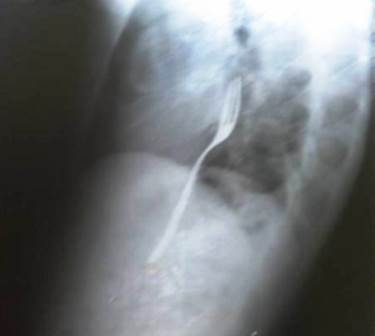

Khi tiến hành chụp X-Quang, các bác sĩ đã phát hiện thấy một vật thể đang án ngự ngay cổ họng. “Tôi đã uống rượu rồi cá cược với một người bạn của tôi rằng mình có thể nuốt được chiếc dĩa mà không bị đau”, Radu Calincescu thừa nhận.

Ảnh chụp X-quang